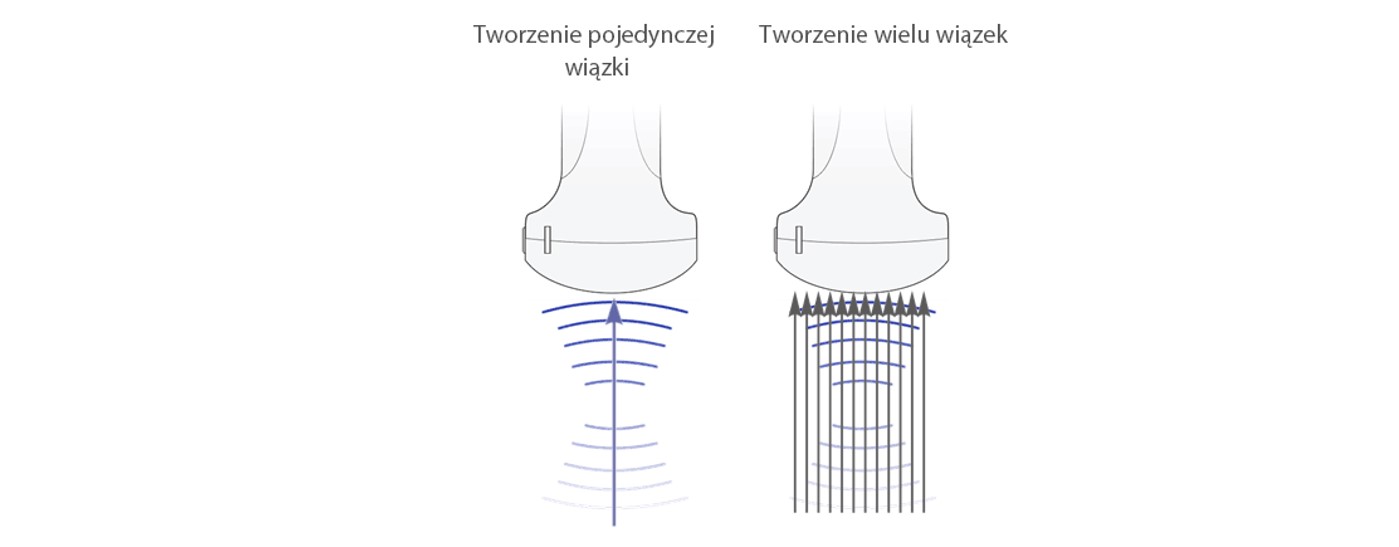

Tworzenie wielu wi?zek

Mo?liwo?? tworzenia maksymalnie 12-krotnego strumienia dla jednej przesy?anej wi?zki, co zapewnia doskona?? rozdzielczo?? czasow? i wy?sz? cz?stotliwo?? od?wie?ania.